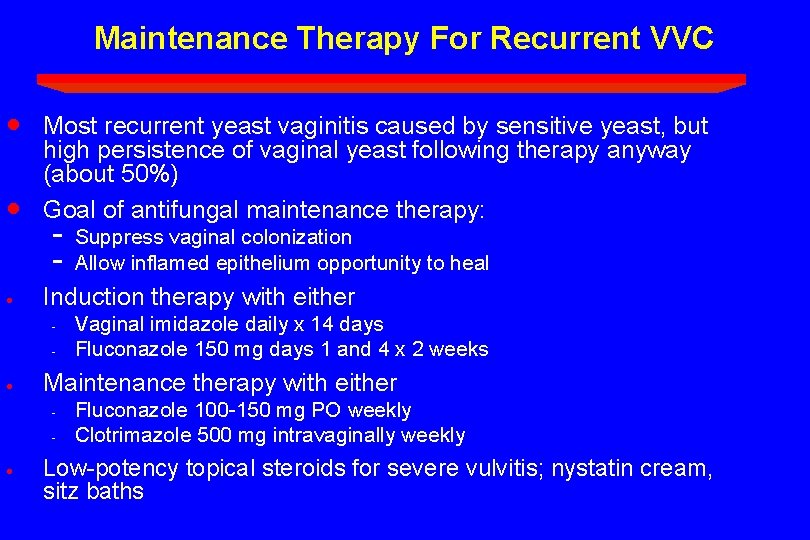

Maintenance Therapy For Recurrent VVC · · Most recurrent yeast vaginitis caused by sensitive yeast, but high persistence of vaginal yeast following therapy anyway (about 50%) Goal of antifungal maintenance therapy: · Induction therapy with either - · Vaginal imidazole daily x 14 days Fluconazole 150 mg days 1 and 4 x 2 weeks Maintenance therapy with either - · Suppress vaginal colonization Allow inflamed epithelium opportunity to heal Fluconazole 100 -150 mg PO weekly Clotrimazole 500 mg intravaginally weekly Low-potency topical steroids for severe vulvitis; nystatin cream, sitz baths